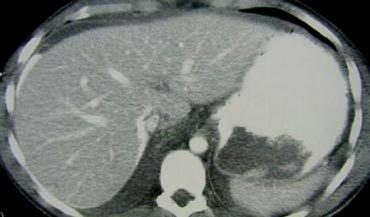

Trước tiên hãy quan sát các hình ảnh bên trái của bệnh nhân bị chấn thương gan.

Các dấu hiệu CT trong trường hợp này là gì?

Các dấu hiệu bao gồm:

- Tụ máu dưới bao gan lớn hơn 10 cm (tức là tổn thương độ 4)

- Vùng ngấm thuốc cản quang (contrast blush) (mũi tên)

- Không có tràn máu ổ bụng kèm theo

Vì vậy, mặc dù có thoát thuốc cản quang, bệnh nhân này sẽ được điều trị bảo tồn (không phẫu thuật) và có thể có tiên lượng tốt, do không có chảy máu vào khoang phúc mạc.

Thoát thuốc cản quang có ý nghĩa đặc biệt quan trọng, nhất là khi kết hợp với tràn máu ổ bụng.